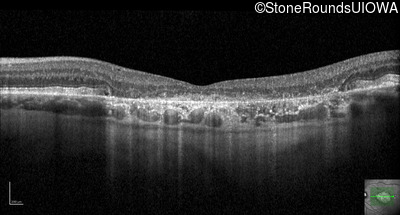

Optical Coherence Tomography - Right - 20/125

Exemplar / OCT Stack